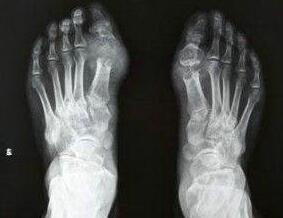

王怀庆主任经过对刘先生脚部痛风症状的观察,对其进行了详细的检查。诊断为痛风急性发作,刘先生右脚大脚趾关节红肿严重,左脚脚背大面积红肿,无法正常走路。尿酸值偏高,需立即降酸及修复功能处理,否则病...[详细]